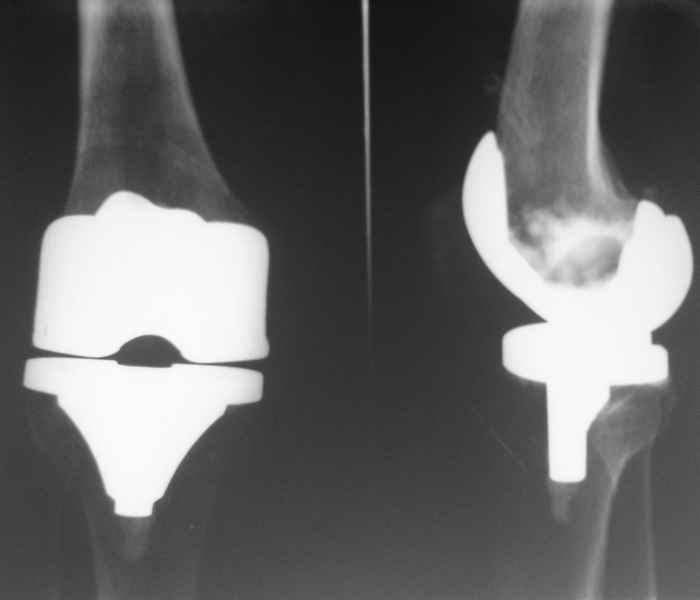

В июле 2007 года выполнена ревизия - полости сустава нет. Капсула сустава имеет толщину от 1 до 1.5 см, собственная связка надколенника имеет толщину до 3 см. Сустав заполнен фиброзно-рубцовой тканью. Компоненты стабильны.

Резецирована капсула, удалены фиброзные ткани из сустава. В области межмыщелковой ямки на бедре обнаружены 2 канала уходящих в мыщелки и проксимально, глубиной до 2 см и диаметром до 1 см. Выскаблены и заполнены синтетическим костным трансплантатом с ванкомицином.Взяты ткани из разных отделов сустава для бак. исследования.

Рана ушита с объемом движений до 70 градусов.По результатам анализов - все стерильно. Как и в посеве крови.